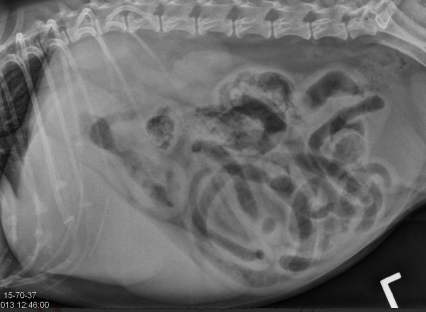

Pheochromocytoma

Medulla = ¼ of adrenal gland

Malignancy of chromaffin cells

local invasion

metastasis

Et: adrenal medulla tumor, excess catecholamines

Epinephrine, norepinephrine

Rare, 12y, dogs>cats

Cs: Restlessness / anxiety / pacing, intermittent collapse, hypertension, PU/PD, tachypnea, Epistaxis, blindness

Dt: CS & PE, imaging, urine normetanephrines

Tx: adrenalectomy (pre-op phenoxybenzamine →α-adrenergic antagonist)